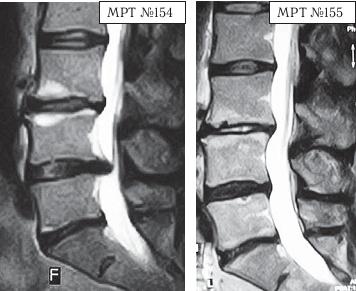

На МРТ № 154 наблюдается состояние поясничного отдела позвоночника после двух операций в сегментах LIII-LIV и LV-SI секвестрированная грыжа межпозвонкового диска в сегменте LIV-LV, абсолютный стеноз спинномозгового канала. На МРТ № 155 — состояние поясничного отдела позвоночника после лечения методом вертеброревитологии. А в этом случае пациента привезли в клинику с целым «букетом» заболеваний позвоночника. ![]() На МРТ № 156 наблюдается состояние поясничного отдела позвоночника после операций: рецидив грыжи межпозвонкового диска в сегменте LIV-LV, абсолютный стеноз спинномозгового канала на этом уровне, спондилёз, эпидурит, арахноидит, наблюдается грыжа межпозвонкового диска в сегменте LV—SI. На МРТ № 157 — состояние поясничного отдела позвоночника после лечения методом вертеброревитологии. Обратите внимание на процессы репаративной регенерации в межпозвонковых дисках в сегментах LIV-LV и LV-SI после лечения данным методом. Следующий случай также по-своему уникален. Это ещё одно прямое свидетельство широкого спектра возможностей вертеброревитологии в решении задач, многие из которых на современном этапе медицины считались неразрешимыми.